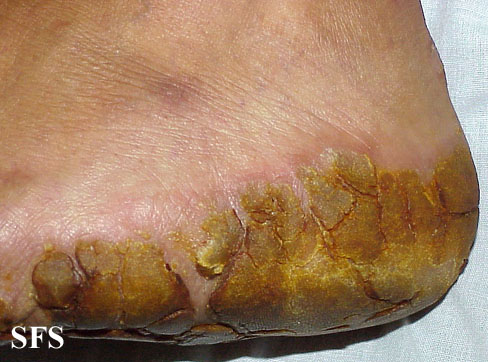

tylotic dermatitis